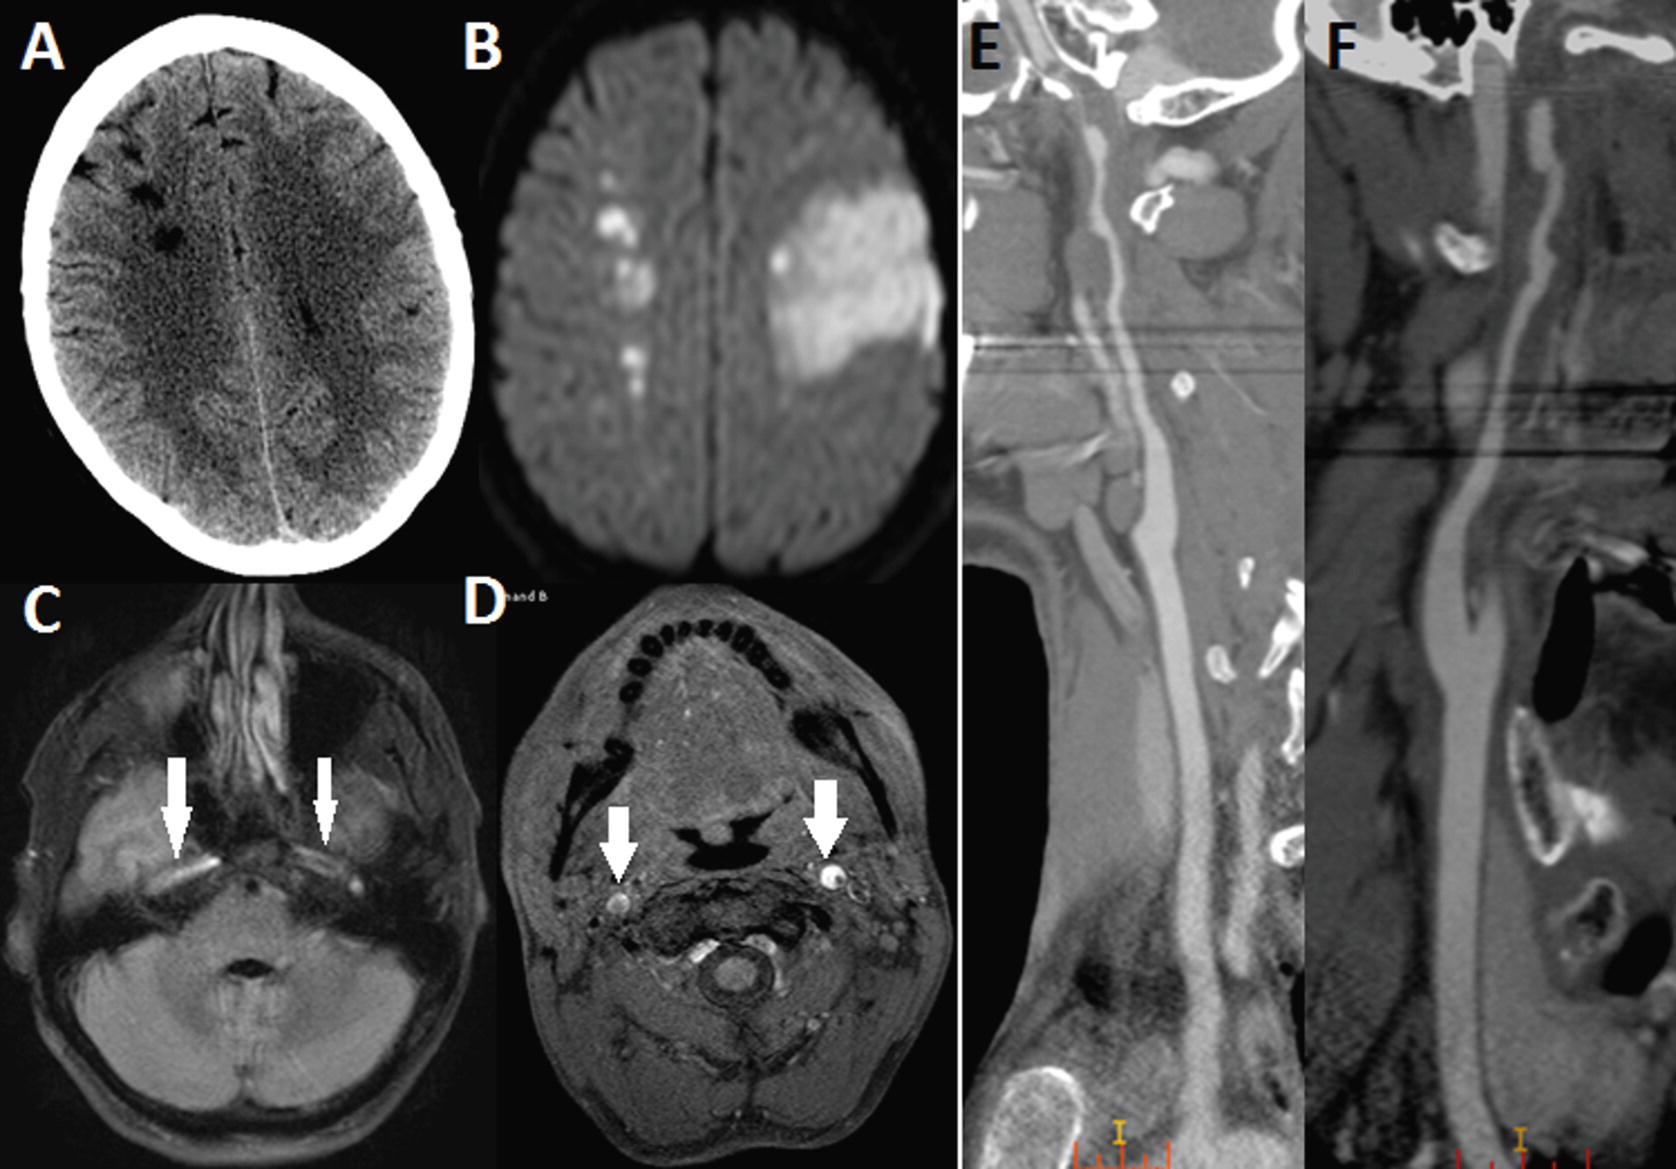

Intraventricular hemorrhage IVH also known as intraventricular bleeding is a bleeding into the brains ventricular system where the cerebrospinal fluid is produced and circulates through towards the subarachnoid spaceIt can result from physical trauma or from hemorrhagic stroke.

30 of intraventricular hemorrhage IVH are primary confined to the ventricular system and typically caused.